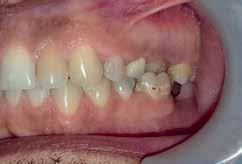

A 33 year old male presented to the orthodontic clinic referred by his prosthodontist . His main concern was the overeruption of maxillary right and left second molar due to bilateral loss of second and third mandibular molars that rendered the placement of prosthodontic implant and crown not possible. The patient had a 4 unit bridge, to replace missing maxillary right first and second premolar, with a root canal treatment and crown done on maxillary right lateral incisor and left second premolar. The patient’s main condition was to reduce the orthodontic system to a minimum with no visible appliances due to the nature of his work in sales.

Endodontic treatment and crown preparation on both maxillary left and right molars to shorten the vertical dimensions of the crowns. This option would require extensive reduction of tooth material due to the fact that upon closure, maxillary second molars were in close proximity with mandibular retromolar area.

Option 2

Placement of temporary anchorage devices (Miniscrew) in the buccal and palatal side of the maxillary second molars in order to orthodontically intrude those teeth and create the required biological space for implant and crown placement in the mandibular posterior molar region(Figure 3).

Interproximal reduction in the area between maxillary first and second molar is necessary to allow the intrusion of the second molar without being hindered by the proximal contact of the first molar.(figure 4)

The patient presented to the clinic every 6 weeks for chain replacement because slow intrusion is needed. The 2nd molar was blocked below the distal contact area of the 1st molar, monitored IPR was carried out between the 1st and 2nd molar on both sides to facilitate the intrusive movement. The treatment took 10 months with 7 appointments.